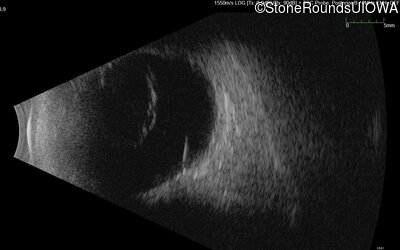

B-Scan Ultrasonography - Right - No Light Perception

Exemplar